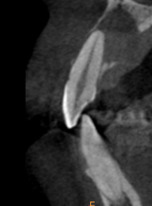

- 治療前

- 治療後

歯科用CTによる精密検査

精密根管治療では、事前に3次元CTを用いた立体的な診断を行います。保険診療では基本的に2次元のレントゲンでの確認となり、精度に差が生まれます。